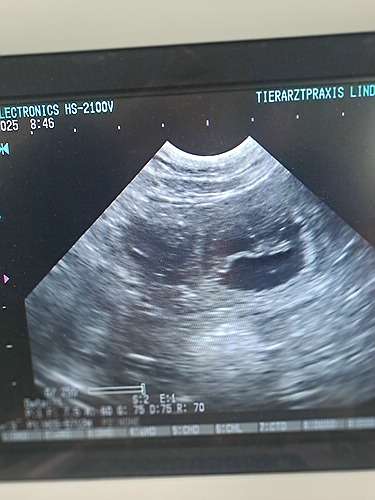

Wir waren am 14.04.25 beim Ultraschall

Stella ist trächtig, wir konnten einige Fruchtanlagen sehen.